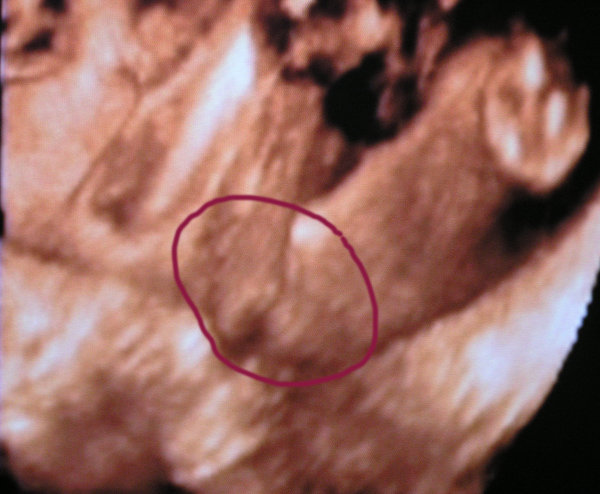

Arcocskánk:

Kép Kép Kép

Hoztam még képet Izabelről,de monitorról lett fotózva,szóval nem vmi jó minőség....

Mindjárt dobok a nuniról is :wink:

Nunink van:

Kép